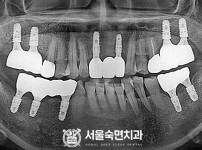

임플란트-전후사진2

치과를-선택할-때-꼭-확인하세요-서울숙면치과-임플란트-전후사진